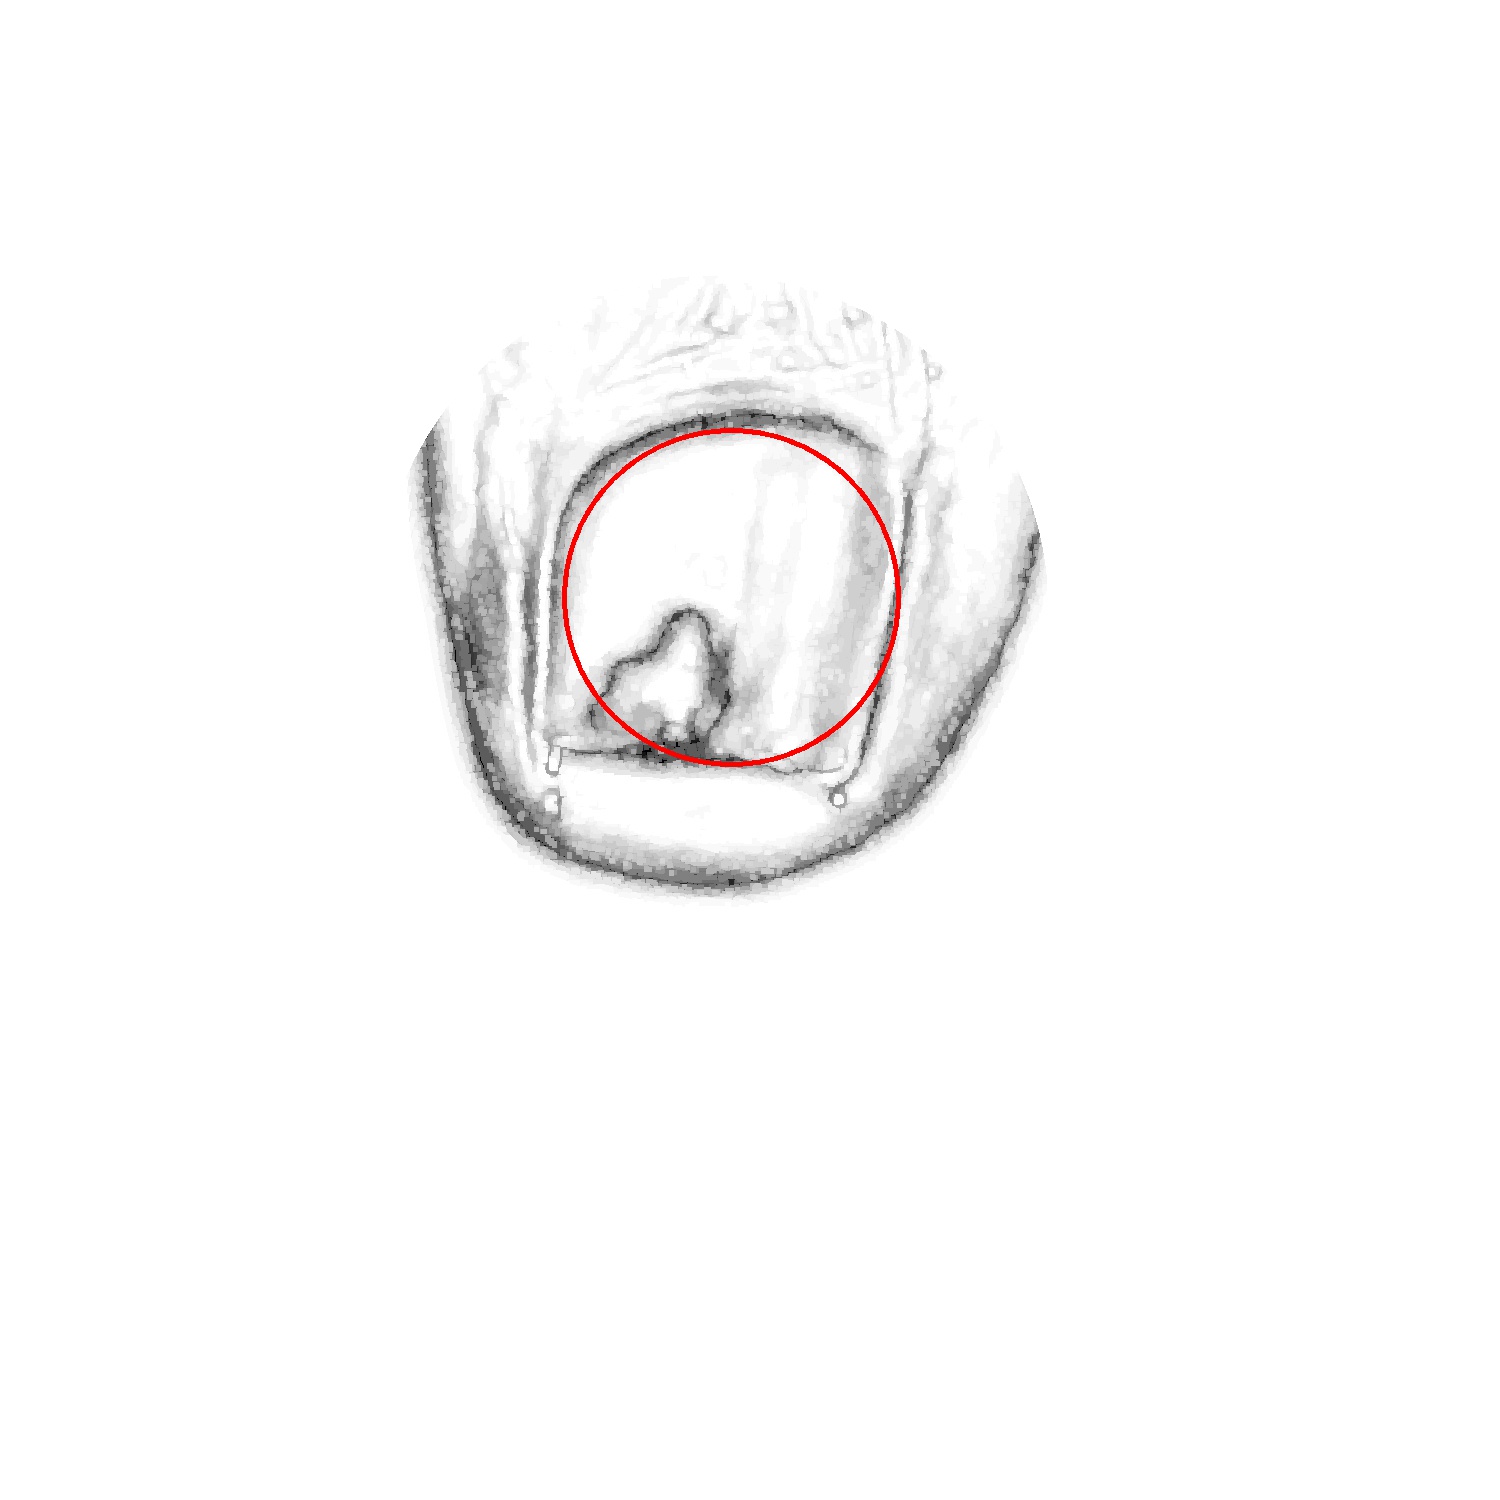

Before tackling the image segmentation problem, we perform an image normalization process based on the template’s known measures. It consists on transforming the input image, as seen in Fig. 3 (left), to an image with standard dimensions and orientation, Fig. 3 (right). To achieve our objective we detect the position of the template corners and geometrically transform the image with an affine mapping. As a result, all normalized images appear to had been taken under the same point of view. We remark that the three template colored squares are mapped to the top-right, bottom-right and bottom-left image corners. In particular, left foot images are mirrored. Normalized images are always set to measure pixels. Since the real region inside the template measures cm, a centimetre in the normalized image accounts for 300 pixels, which can be used to measure distances and areas.

In order to select the tip of the toe, we segment the foot regions from the background template. Then, the Hough transform is used to detect a circle in the foot region, which corresponds to the tip of the toe. Next, the nail is found within the tip of the toe using a second Hough transform, that depends on the result of the first one. Specifically, this second Hough transform is computed taking into account only the edges that are in the tip of the toe circular estimation. In the following, we detail the transformations performed.

Onto that edge image, we apply the Hough transform to locate the tip of the toe. Due to its position and size, the area inside this pattern contains the nail. So, we apply the circular Hough transform on the edge image and we select the best candidate as the nearest circle to the template bottom right corner that has a predefined percentage of its area within the foot ROI (specifically, we choose a threshold of ). Also, the computed circles are limited to radius between 0.85 cm and 1.75 cm. The selected circle is shown in Fig. 5(b). We remark that this circular pattern captures the tip of the toe but does not locate the nail with acceptable accuracy.

Finally, we detect the circle that better fits the nail using a second Hough transform. We discard the edges far from the tip of the toe circle (see Fig. 5(c)), so that we mainly keep the nail edges. Thus, this second Hough transform is prone to detect the circle that best fits the nail. Also, we constrain the radius of this circle according to the size of the tip of the toe. Specifically, we expect the nail radius to be smaller than the radius of the tip of the toe circle (see Fig. 5(b)) but bigger than half of its measure. The most prominent circle (see Fig. 5(d)) is the one selected as nail circle. Experimentally, the results of this process have proved to always find a location on the nail (the circle center) and a good estimation of the nail size (derived from the radius).

In Fig. 7(a), we can appreciate that the contours of the nail are sharp. Thus, provided the initial markers are corrected, the growth of the nail and skin regions would be prone to stop at these edges. This has been actually the case when processing images in practice, as shown in Fig. 7(d).